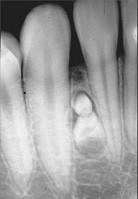

组图为牙瘤的外观及X 线表现,有关此病的描述错误的是 ( )

组图为牙瘤的外观及X 线表现,有关此病的描述错误的是 ( )![]()

A绝大多数为恶性

B生长缓慢,早期无自觉症状

C由牙胚组织异常发育增生而形成

DX 线可见类似发育不全牙的影像

E多见青年人